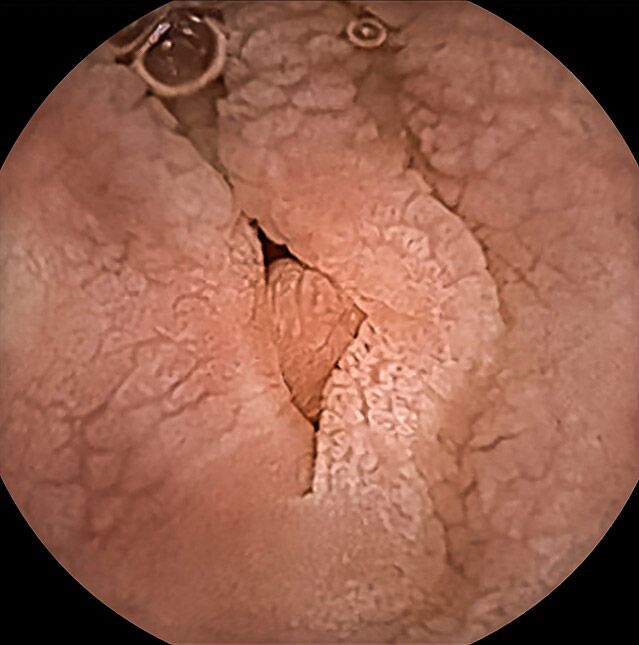

Die Kapselendoskopie hat sich als diagnostischer Goldstandard für die Beurteilung des Dünndarms etabliert. Mit ihr ist es möglich, nicht invasiv, schmerzfrei und ohne Strahlenbelastung den gesamten Dünndarm von innen zu untersuchen. Der Dünndarm ist sonst mit seiner Länge von etwa fünf Metern einer konventionellen Endoskopie nicht vollständig zugänglich.

Die wichtigste Indikation ist die Abklärung einer weder aus dem Magen noch aus dem Dickdarm stammenden Blutung (eine sogenannte mittlere Darmblutung). Eine Magen- und Darmspiegelung müssen zeitnah vorher erfolgt sein.

Die verwendete Videokapsel „Kamerapille“ ist eine winzige Digitalkamera, die einschließlich Licht-, Batterie- und Funktechnik nur etwa die Größe eines Gummibärchens hat. Auf ihrem Weg durch den Magen-Darm-Kanal nimmt die Kapsel automatisiert Bilder der Schleimhaut des Verdauungstraktes auf und sendet sie nach außen an einen tragbaren Datenrekorder. Die von uns verwendete neueste Kapselgeneration passt sogar die Bildfrequenz der Geschwindigkeit an, mit der sich die Kamerakapsel im Darm bewegt und kann kleinste Objekte bis zu einer Größe von 0,7 mm erkennen.